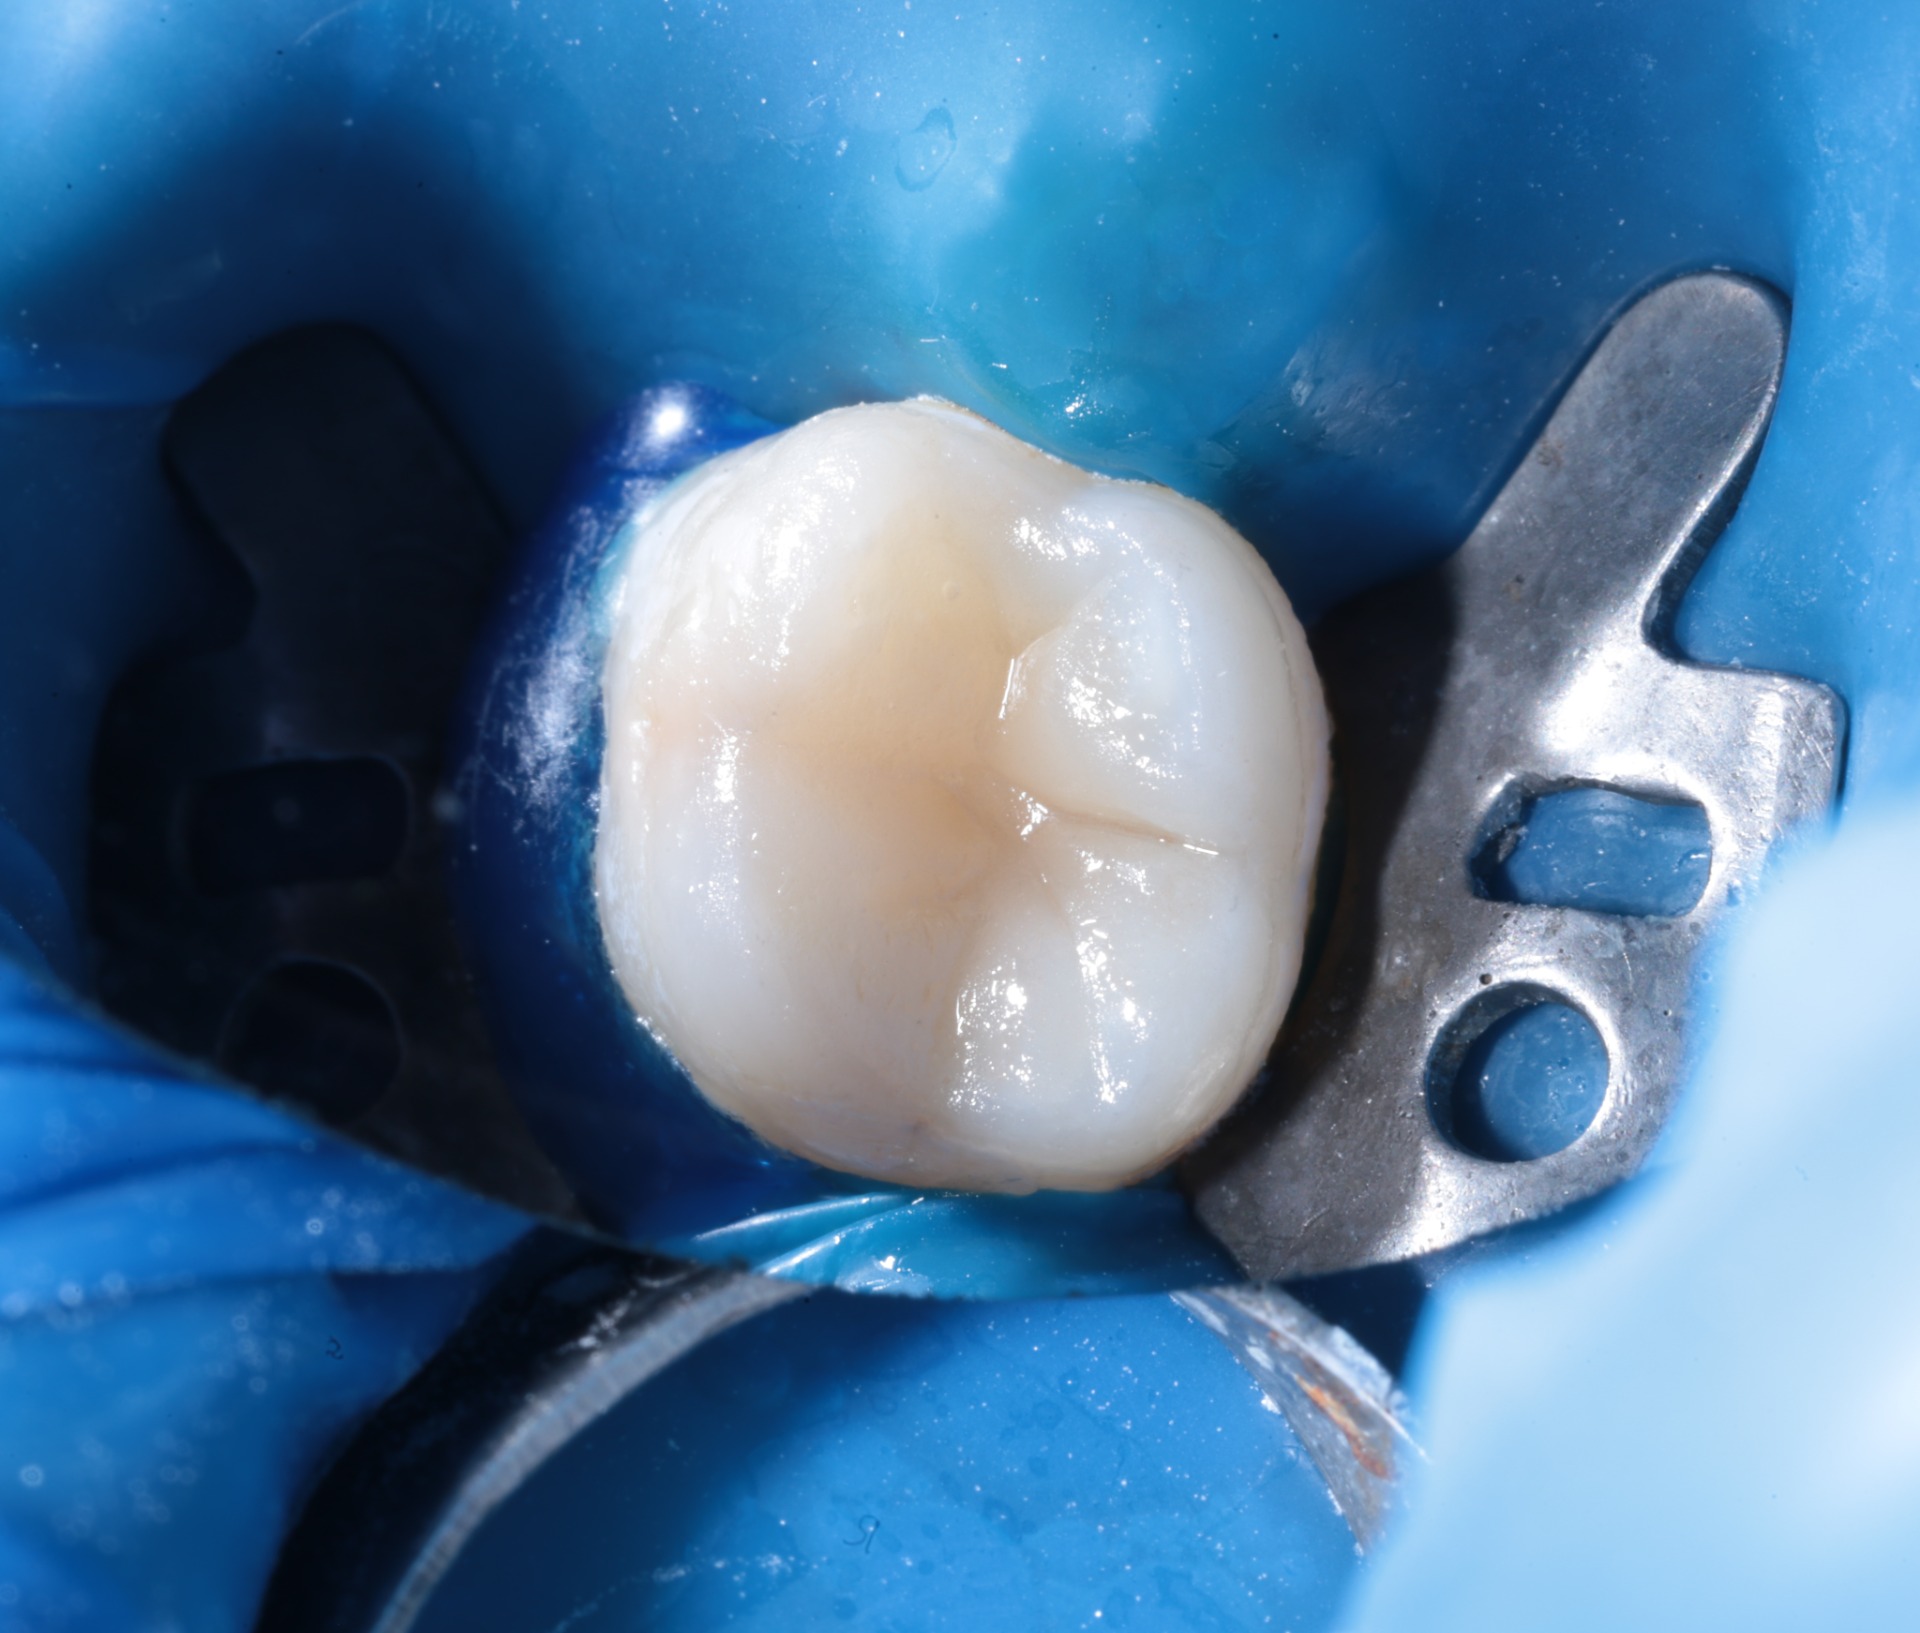

Реставрація зубів

Естетичне відновлення реставраціями — коли зуб виглядає як новий за один візит.